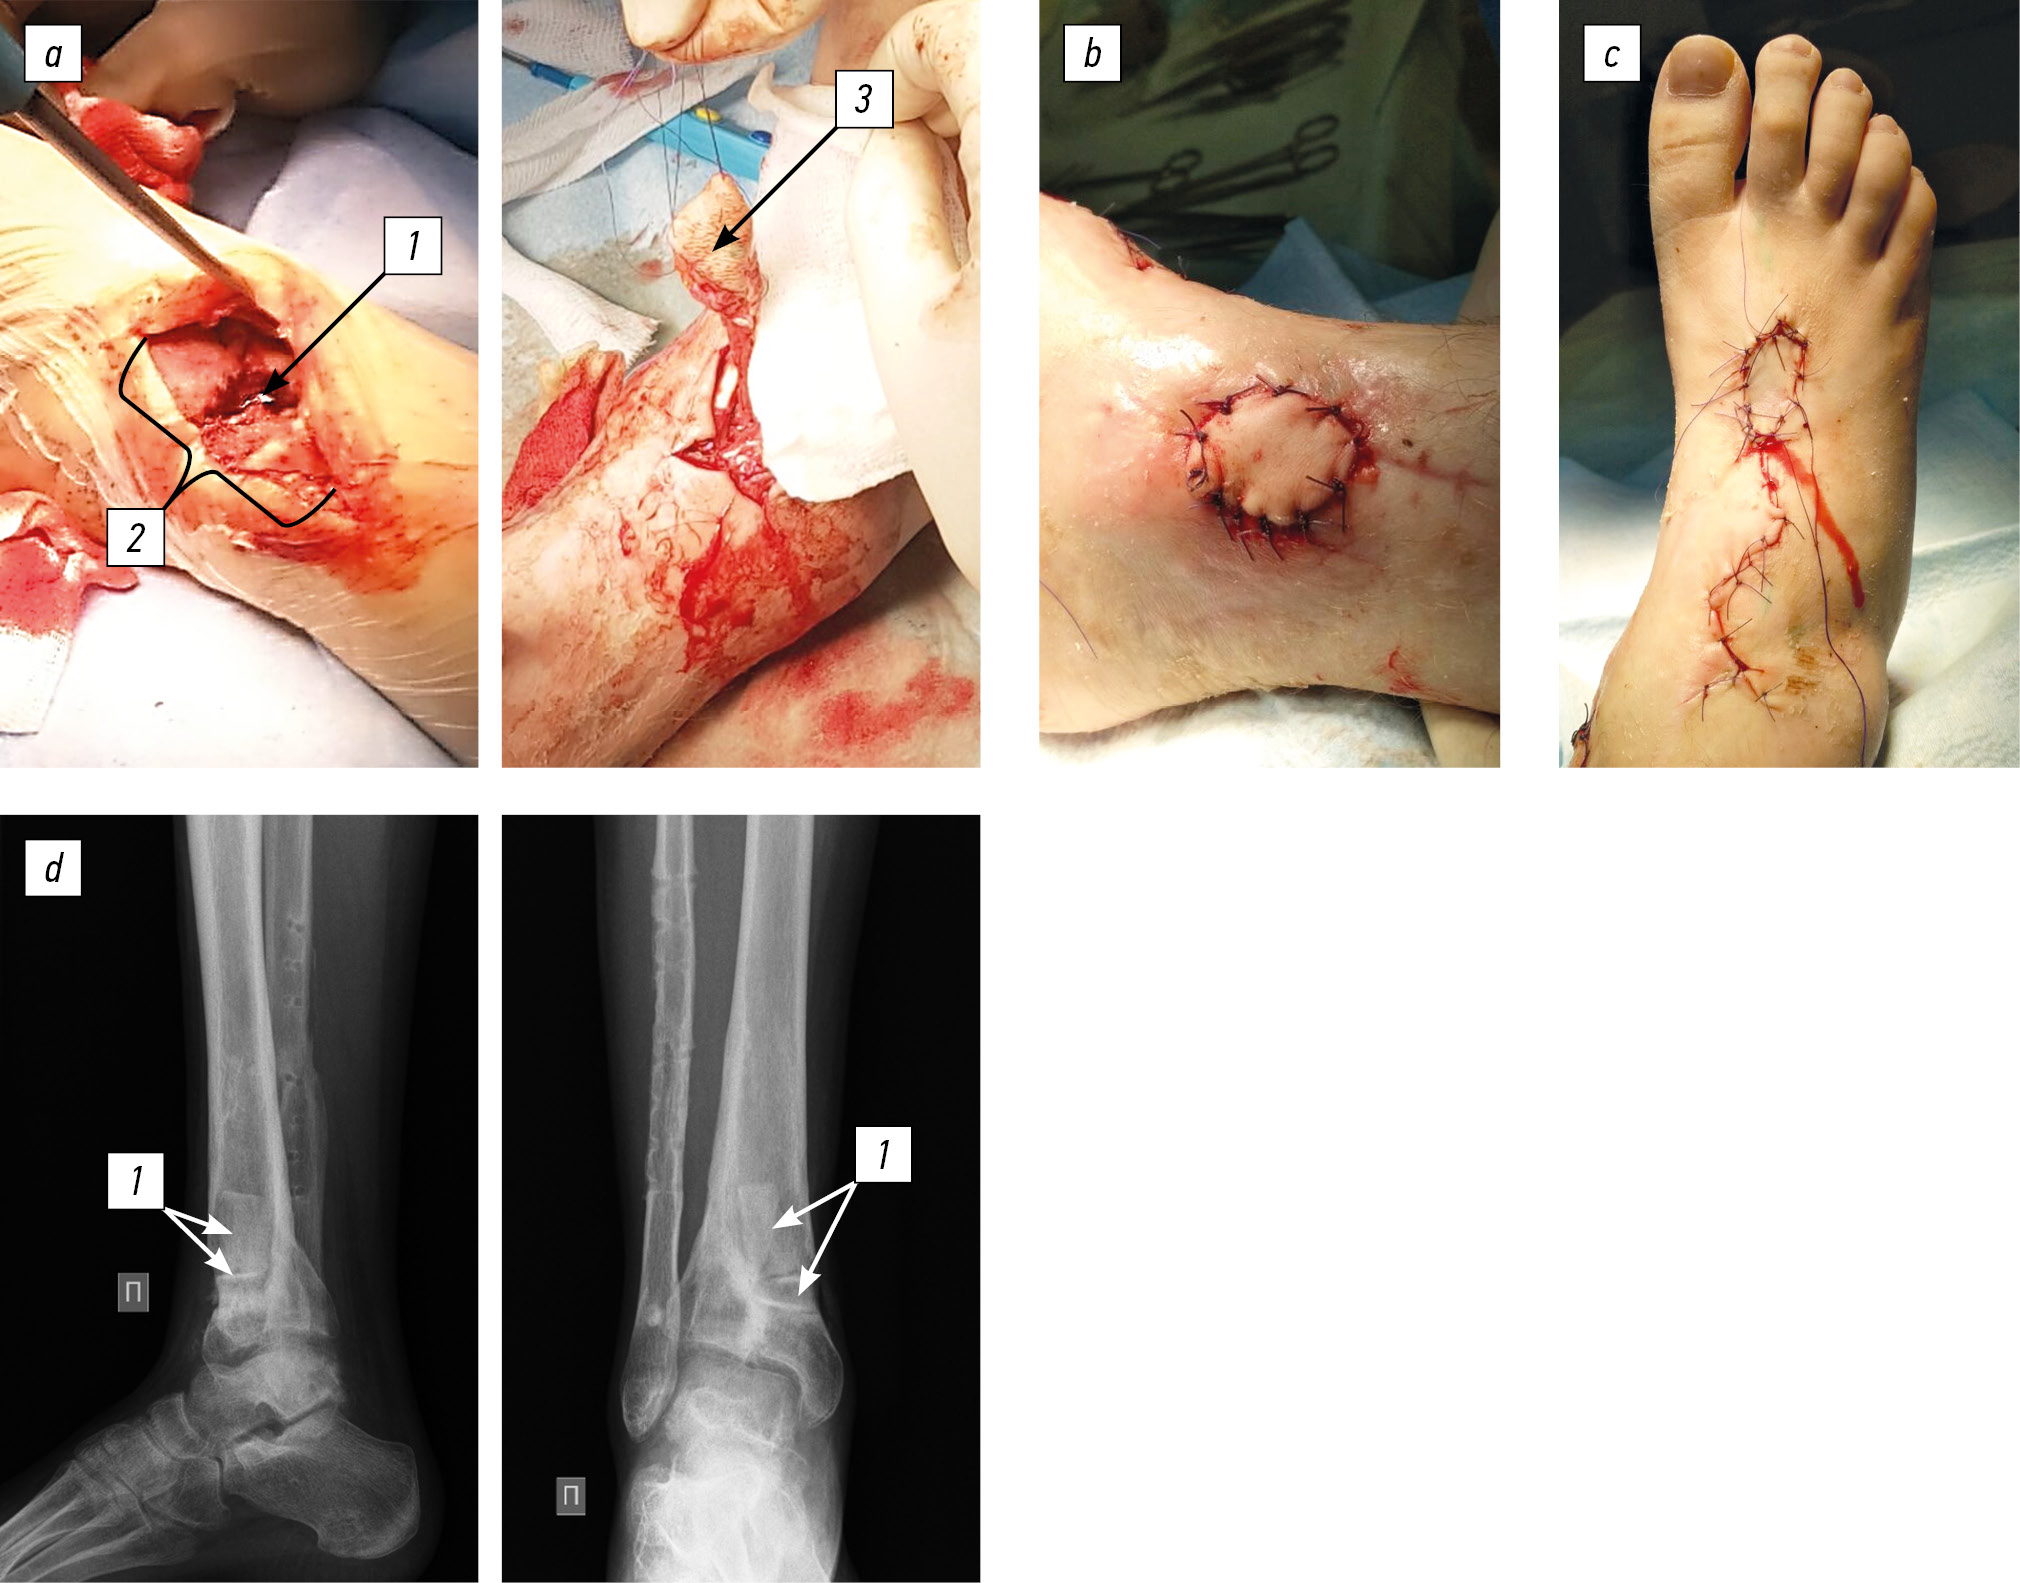

Status localis. The patient walks without aids and limps on the right limb. On the anterior inner surface of the leg in the lower third, a fistula of up to 5 mm in diameter was present, the skin around the fistula (up to 4 cm in diameter) was hyperemic and macerated, with cicatricial changes and scanty serous-purulent discharge (Fig. 4a). Palpation was moderately painful. Toe movement and sensitivity were preserved, and capillary response from the nail plates was brisk. The absolute length of the lower extremities was D < S per 1 cm. X-ray images of the right lower leg revealed a defect in the distal metaphysis of the tibia up to 1/2 the diameter, limited to a zone of sclerosis, proximal to the defect at the level of the metadiaphysis, a heterogeneous bone structure with small cysts, and undefined physeal zone. The fibula fracture consolidation with metal extracortical osteosynthesis was satisfactory (Fig. 4b).

Fig. 4. An 11-year-old female patient diagnosed with chronic post-traumatic osteomyelitis of the right tibia: a, appearance of the limb and the fistulous process; b, radiographs of the right ankle joint in two views

Considering the course of chronic osteomyelitis, complicated by a fistulous process with trophic changes in soft tissues, radical reconstructive intervention was decided, which included the removal of the hardware of the right fibula, fistulectomy of the lower third of the right tibia, osteonecrectomy of the distal metaphysis of the right tibia, bone autografting of the defect (iliac crest), plastic surgery of a wound defect using an islet dorsal foot graft with axial blood flow, and plastic surgery of the donor wound with a split skin graft (Fig. 5). Histological examination revealed chronic nonspecific inflammation with exacerbation, and bacteriological examination revealed S. aureus 103 with high sensitivity. The patient received a course of antibacterial therapy with cefazolin at an age-appropriate dose. In dynamics, the infectious and inflammatory process stopped. Control radiographs after 6 months showed the integration of bone grafts (Fig. 6). The support ability of the limb has been restored; when walking >1.5 km, she experienced pain (up to 3 points on the visual analog scale) in the ankle joint. The shortening did not increase during the follow-up period.

Fig. 5. Surgical wound (a): 1, zone of destruction; 2, wound defect after excision of the fistula; 3, dorsal foot flap on a vascular pedicle. The wound defect after fistulectomy is closed with a vascularized graft (b), a donor wound (c), control radiograph of the ankle joint in two views, and bone autoplasty of the tibial defect is determined (d): 1, bone grafts

Fig. 6. Control radiographs after 6 months and integration of bone grafts without signs of an infectious–destructive process